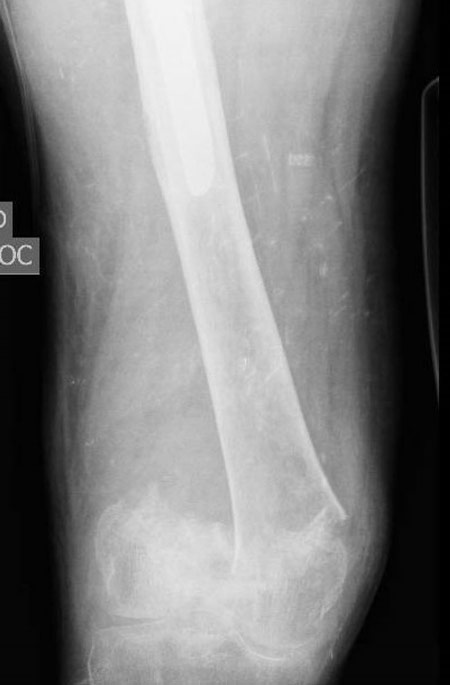

Pre-op x-ray